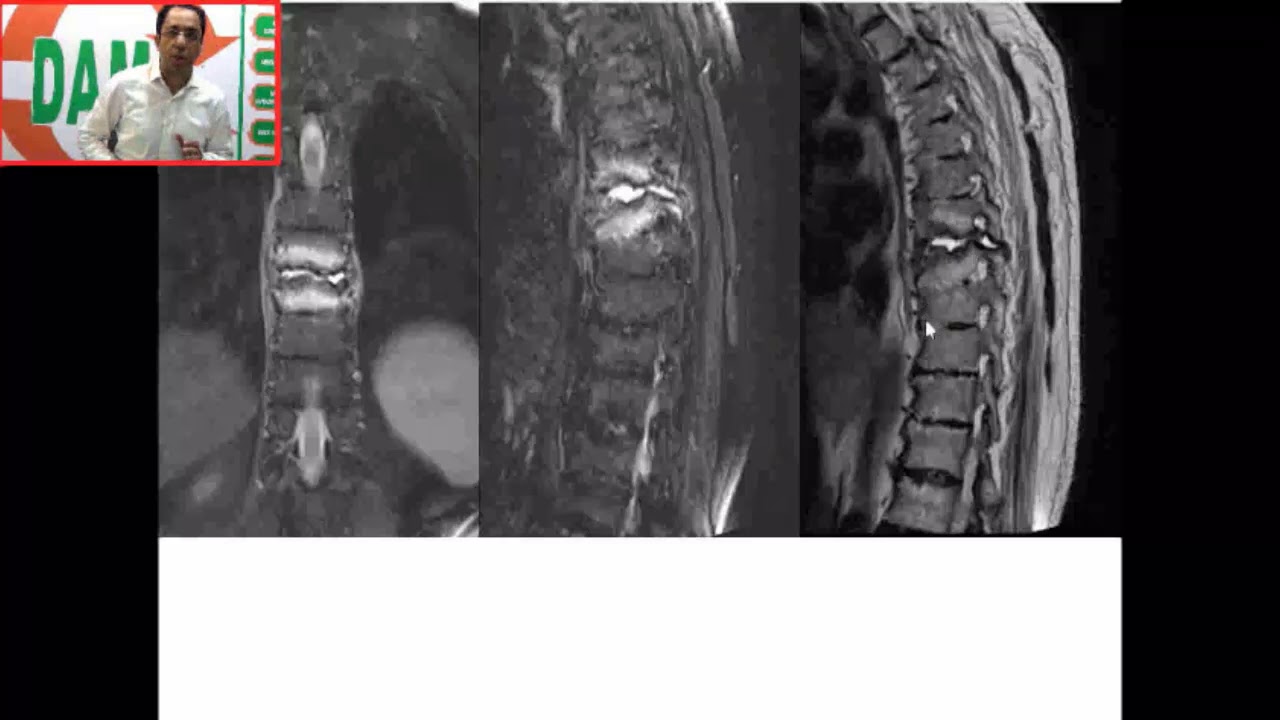

Temporal Bone CT | Radioclinical Perspective

Описание: #Dams #Unplugged #Temporal Bone #CT #Radio clinical Perspective

#DAMS #Unplugged #Ankylosing #Spondylitis #Complication